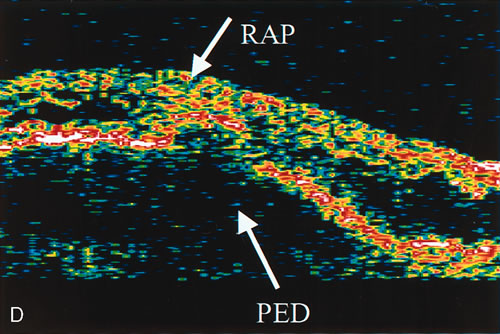

zone in senile macular degeneration. Am J Ophthalmol 93:157, 1982. 8. Yannuzzi LA, Negrão S, Iida T et al: Retinal angiomatous proliferation in age-related macular degeneration. Retina 21:416–434, 2001. 9. Fernandez LH, Freund KB, Yannuzzi LA et al: The nature of focal areas of hyperfluorescence or hot spots imaged with

indocyanine green angiography. Retina 22:557–568, 2002. 10. Ghazi NG. Retinal angiomatous proliferation in age-related macular degeneration. Retina 22:509–511, 2002. 11. Axer-Siegel R, Bourla D, Priel E et al: Angiographic and flow patterns of retinal choroidal anastomoses in age-related

macular degeneration with occult choroidal neovascularization. Ophthalmology 109:1726–1736, 2002. 12. Lafaut BA, Aisenbrey S, Vanden Broecke C et al: Clinicopathological correlation of deep retinal vascular anomalous complex

in age related macular degeneration. Br J Ophthalmol 84:1269–1274, 2000. 13. Slakter JS, Yannuzzi LA, Schneider U: Retinal choroidal anastomoses and occult choroidal neovascularization in

age-related macular degeneration. Ophthalmology 107:742–753, 2000. 14. Hartnett ME, Weiter JJ, Staurenghi G et al: Deep retinal vascular anomalous complexes in advanced age-related

macular degeneration. Ophthalmology. 103:2042–2053, 1996. 15. Kuhn D, Meunier I, Soubrane G et al: Imaging of chorioretinal anastomoses in vascularized retinal pigment epithelium